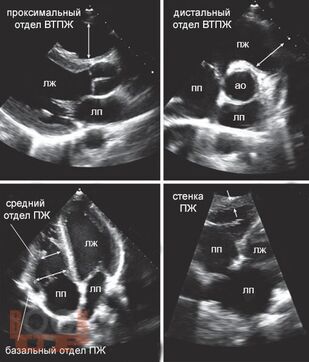

Издание содержит многочисленные рисунки и схемы, иллюстрирующие расстройства гемодинамики, методы исследования и современные оперативные вмешательства при клапанной патологии. Приведены также нормативные данные о размерах сердца и его структур, что необходимо в практической врачебной деятельности.